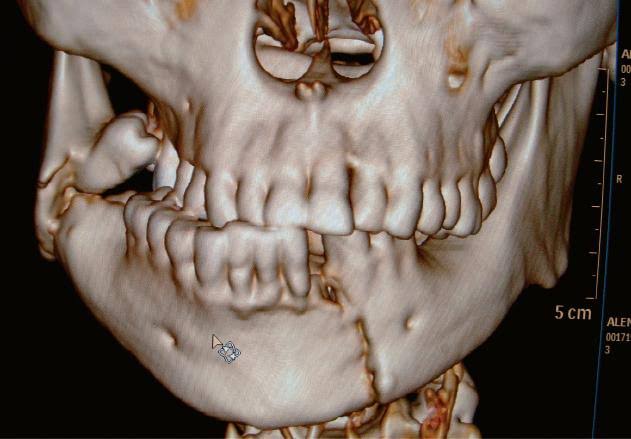

Oral Accidental & Fracture

Accidental tooth fractures can be sudden and distressing, but timely treatment can restore your smile and prevent further damage. Whether it’s a minor chip or a significant break, addressing the issue promptly ensures the best outcomes for your dental health.